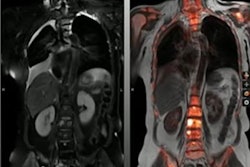

Dr. Adriano Dias highlighted results of a trial using Pylarify radiotracer in selecting patients for focal ablative therapy. Image courtesy of Adriano Dias.

Dr. Adriano Dias highlighted results of a trial using Pylarify radiotracer in selecting patients for focal ablative therapy. Image courtesy of Adriano Dias.Forty out of 67 (60%) lesions identified in patients on PET, mpMRI, or PET/MRI were malignant, and 34 of these 40 (85%) were clinically significant, according to the findings. On a lesion-level analysis in these, the sensitivity of PET was higher than of mpMRI and PET/MRI (91% vs. 76% and 79%), but it showed a lower specificity (39% vs. 85% and 88%, p < 0.001). The calculated AUCs were 0.65 for PET, 0.81 mpMRI, and 0.84 for PET/MRI.